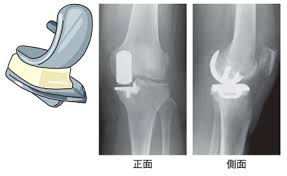

무릎관절은 체중을 가장 많이 지탱하는 관절입니다. 나이가 들수록 연골은 점차 마모되고, 충격을 흡수하는 능력도 감소합니다. 이로 인해 통증, 뻣뻣함, 운동 제한이 생기며, 이런 증상이 악화되면 인공관절 수술이 필요해집니다.

퇴행성 관절염 외에도 류마티스 관절염이나 외상 후 관절 손상이 심각할 경우 수술이 권유되며, 수술을 통해 환자는 통증 없이 보행이 가능해지고 일상생활로 복귀할 수 있게 됩니다.